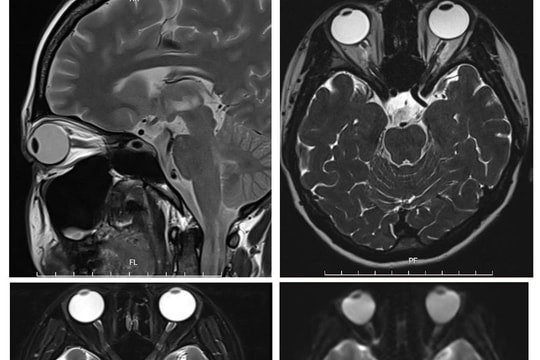

Nhầm lẫn với tiền đình, người phụ nữ mắc hội chứng thần kinh hiếm gặp

Gặp triệu chứng chóng mặt, tê bì tay chân, mất thăng bằng, người phụ nữ chủ quan nghĩ mình bị tiền đình, tuy nhiên căn nguyên lại là một hội chứng thần kinh nguy hiểm và hiếm gặp.

“Giải thoát” nữ bệnh nhân khỏi bệnh rối loạn phổ viêm tủy thị thần kinh thể hiếm gặp

Bệnh viện Đa khoa tỉnh Phú Thọ thông tin về việc đơn vị vừa điều trị thành công cho một trường hợp rối loạn phổ viêm tủy thị thần kinh thể hiếm gặp.